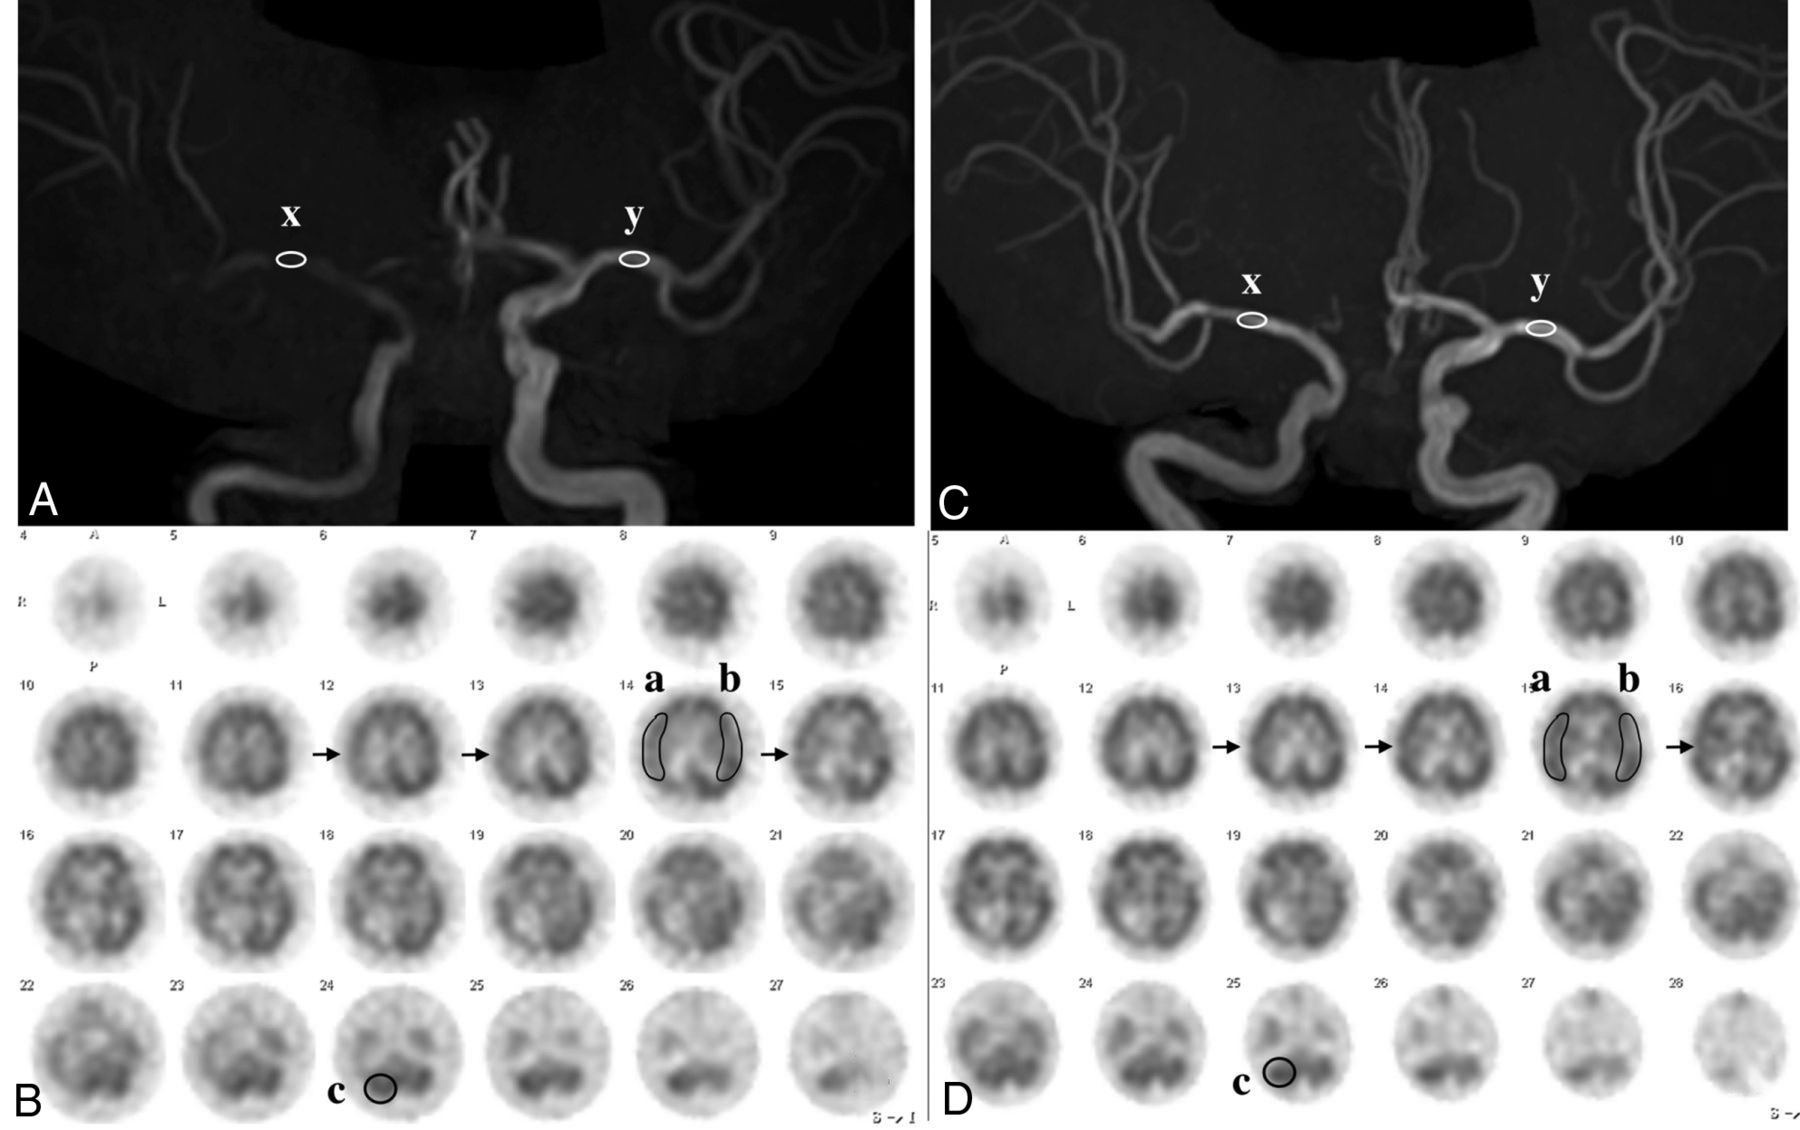

MRA and SPECT in the same case as in Fig 1. A, MRA before CAS reveals an MCA rSI value of 0.44: [(x: 784) divided by (y: 1775)]. B, SPECT before CAS demonstrates a CBF decrease in the right MCA territory (arrows). AI was 80.3%% [(a: 31.94) divided by (b: 39.78)], and rCBF% was 83.9% [(a: 31.94) divided by (c: 38.07)]. C, MRA after CAS reveals an MCA rSI of 1.16: [(x: 2967) divided by (y: 2667)]. D, SPECT after CAS demonstrates a CBF increase in the right MCA territory (arrows). AI% was 92.7% [(a: 37.95) divided by (b: 40.93)] and rCBF% was 99.9% [(a: 37.95) divided by (c: 37.99)]. rSI indicates relative signal intensity.